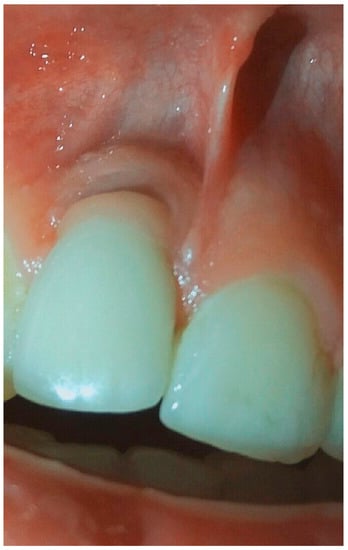

Figure 8.

Condition of soft tissue near dental implant in 1.1 position after treatment in 6 months.

Figure 9.

X-ray of patient in 6 months after treatment.